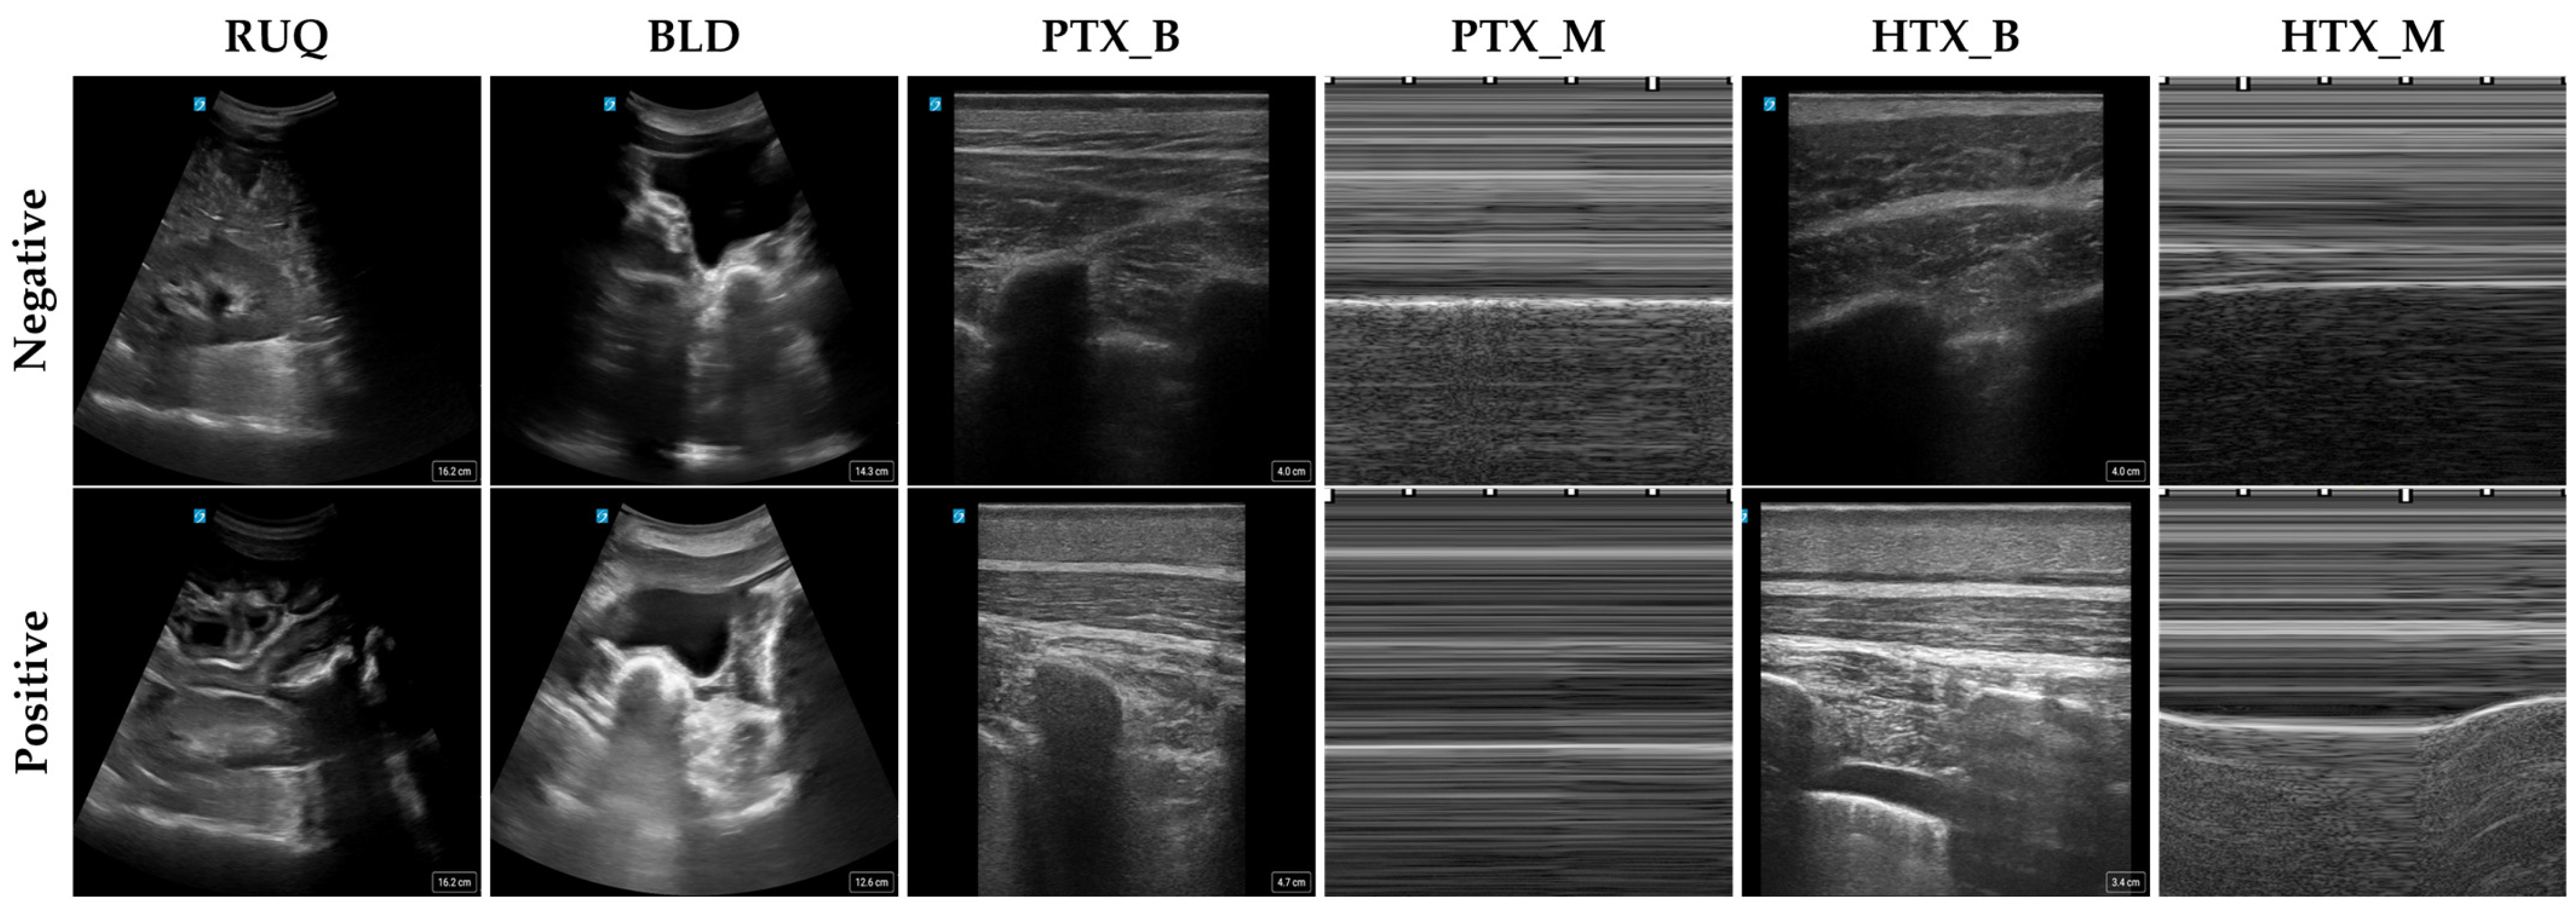

2.1. Data Collection

| Scan Point | RUQ | BLD | PTX_B | PTX_M | HTX_B | HTX_M |

|---|---|---|---|---|---|---|

| Positive Images | 30,000 | 20,845 | 34,957 | 4525 | 76,431 | 9368 |

| Negative Images | 31,396 | 22,049 | 54,420 | 6425 | 54,420 | 6425 |

| Total Number of Images | 61,396 | 42,894 | 89,377 | 10,950 | 130,851 | 15,793 |

| Subjects | 25 | 21 | 22 | 20 | 25 | 25 |